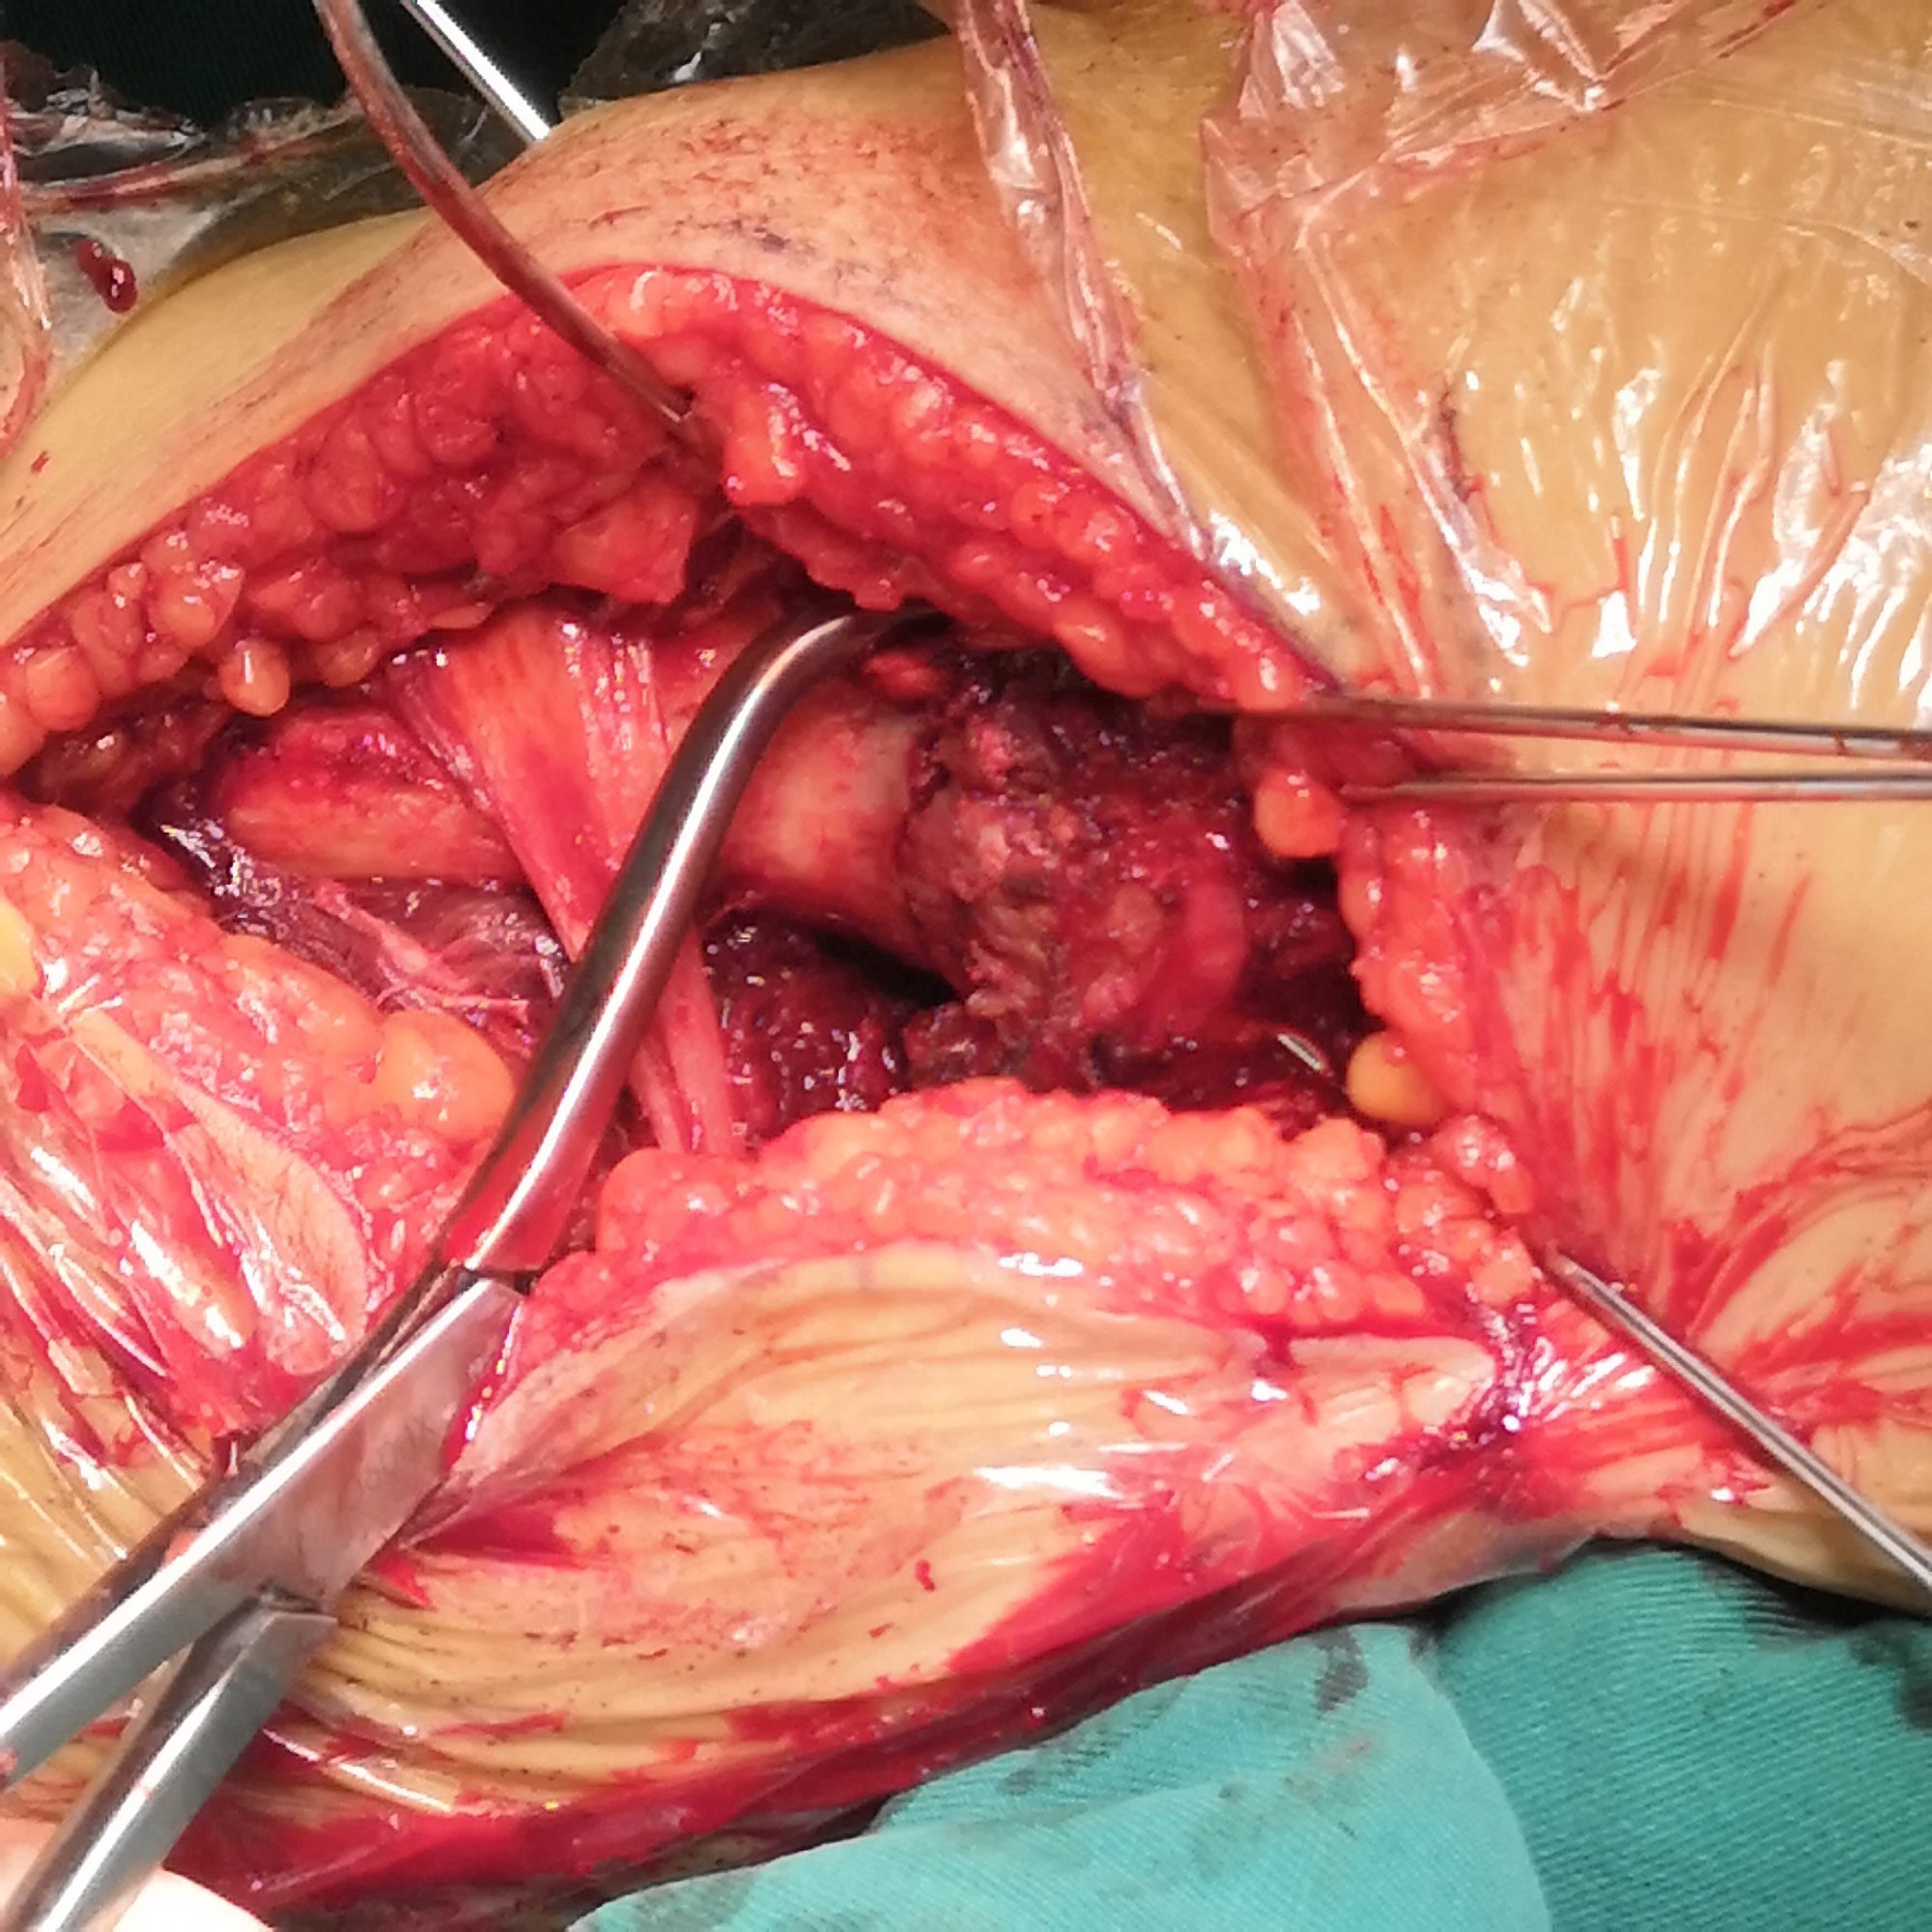

切开探查

进一步复位、植骨内固定